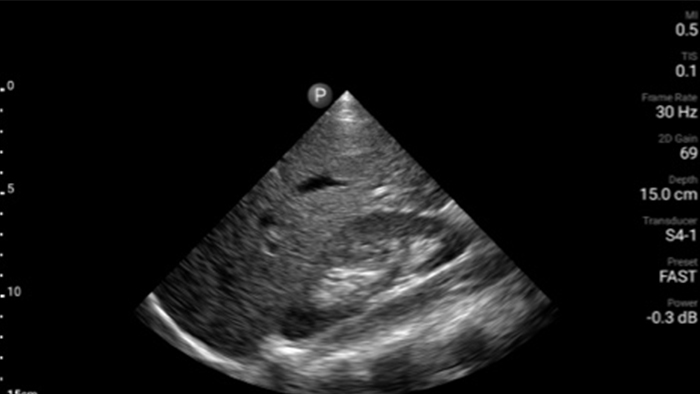

Act faster to protect their heart

When seconds count, portable ultrasound can make the difference. Lumify can provide the high-definition imagery you need whenever and wherever you need it.

Lumify S4-1 broadband phased array transducer